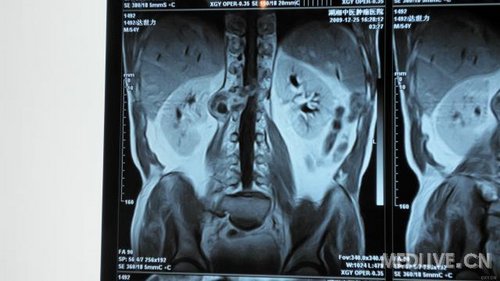

串者因腰椎间盘突出入院治疗,但询问病史查体时发现患者近1月来出现右腹股沟处麻木,局部感觉减退。做MRI等检查发现L1、2处椎管肿瘤。准备行手术治疗,但患者经济困难。各位专家指点一下选什么手术入路对脊柱稳定性影响比较小,尽量不上内固守。

还有MRI片

还有MRI片.